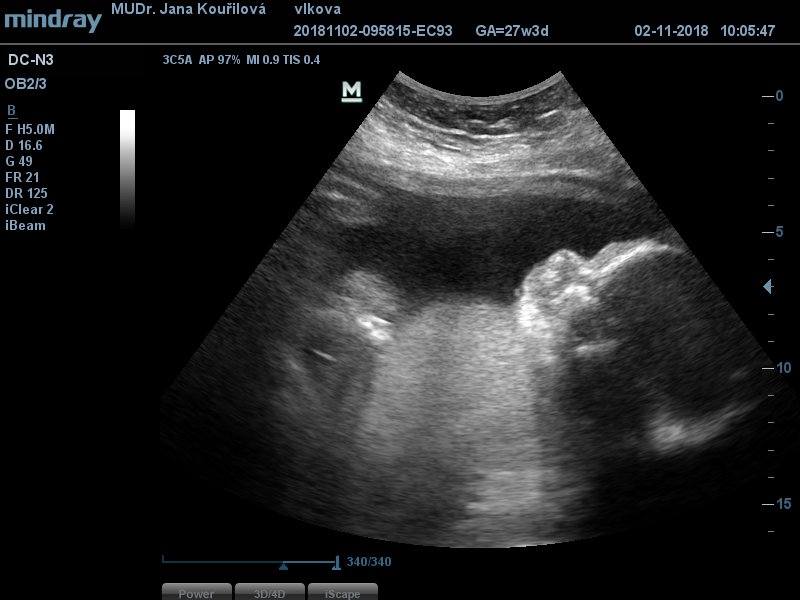

já jsem se dneska na všechno vyprdla a nešla jsem do práce, ale zůstala doma. Muž má volno, tak Jiřík nešel do školky a měli jsme rodinný den :D Dopo jsme byli u mamky orat políčko, po o jsem zazimovala zbytek kytek a teď přivezl švagr synovce, poprvé co se rozešli si ho mohl vzít, nicméně jde zítra do práce a já ho budu hlídat, ale ti dva kluci dohromady, to je pohroma....Když nedala fotku @sonisek tak zaspamuju aspoň já...náš Igoušek,..1040g....v pondělí budou výsledky krve, tak budu celý víkend nervní...